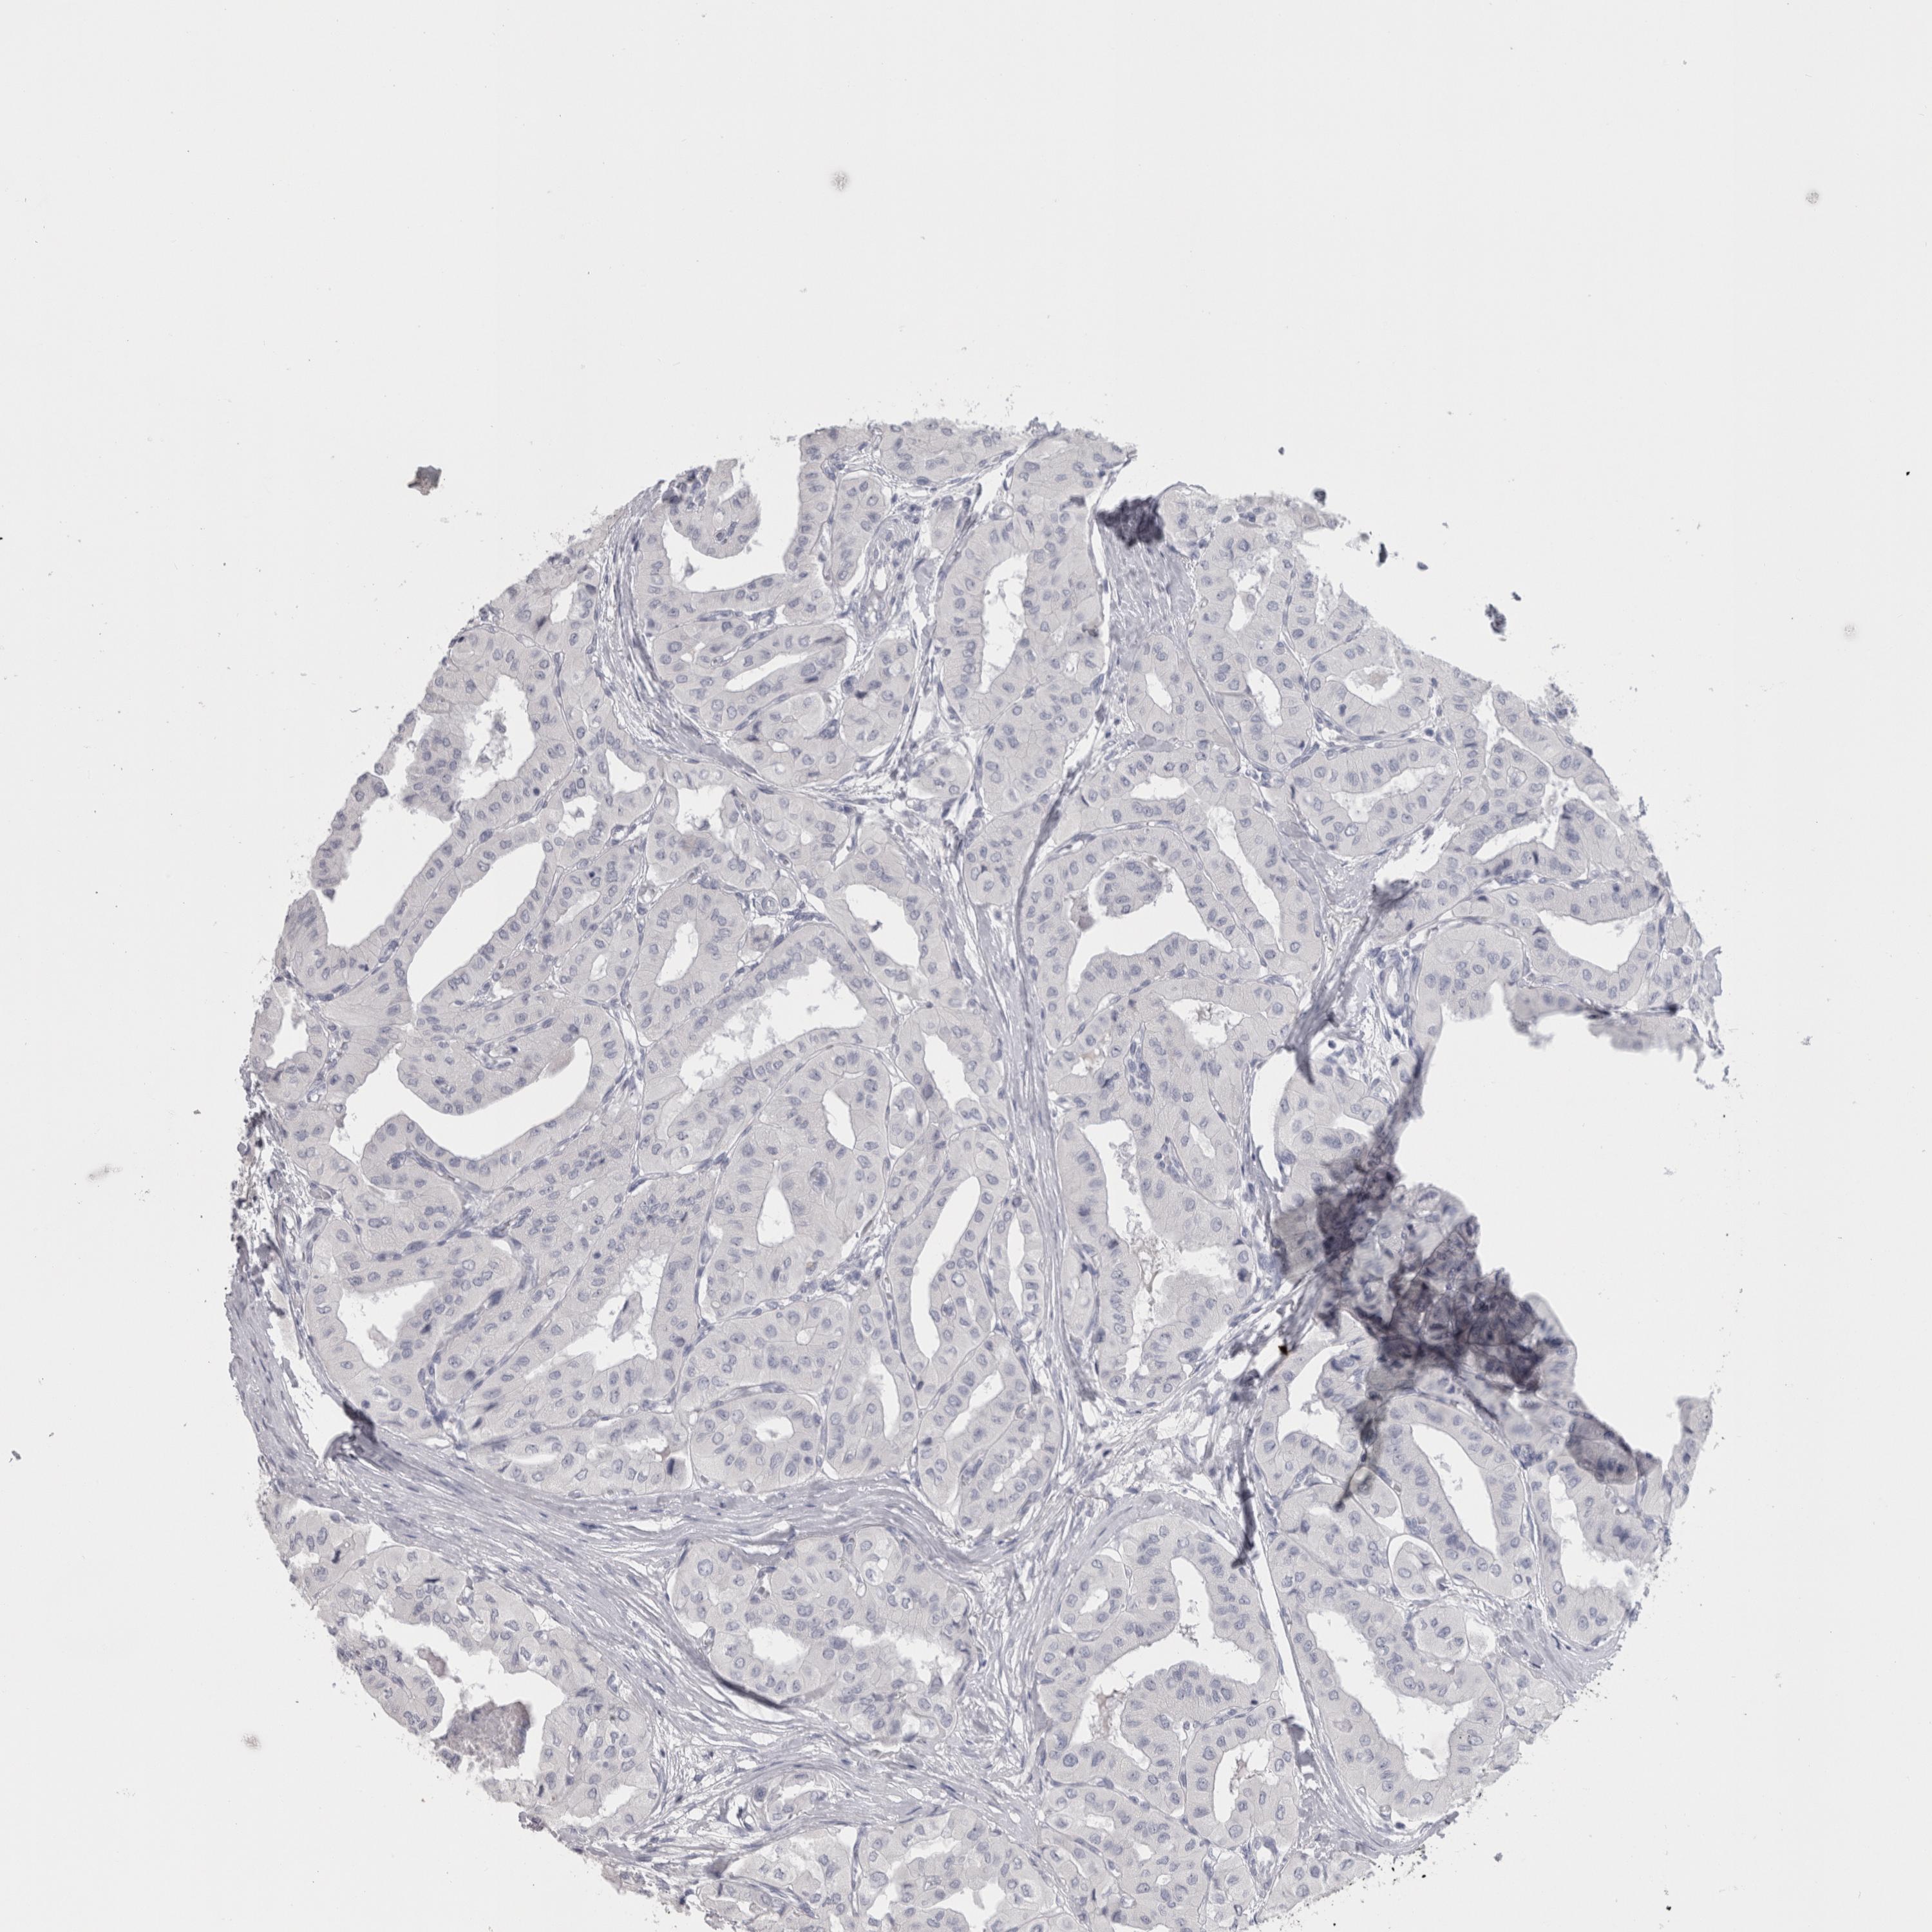

THYROID CANCER - Protein expressioni

A mouse-over function shows sample information and annotation data. Click on an image to view it in a full screen mode. Samples can be filtered based on level of antibody staining by selecting one or several of the following categories: high, medium, low and not detected. The assay and annotation is described here.

Note that samples used for immunohistochemistry by the Human Protein Atlas do not correspond to samples in the TCGA dataset.

Antibody stainingi

Antibody staining in the annotated cell types in the current human tissue is reported as not detected, low, medium, or high, based on conventional immunohistochemistry profiling in selected tissues. This score is based on the combination of the staining intensity and fraction of stained cells.

Each image is clickable and will lead to virtual microscopy that enables deeper exploration of all samples and also displays staining intensity scores, fraction scores and subcellular localization as well as patient and tissue information for each sample.

Antibody HPA051257

Antibody CAB026357

Staining

High

Medium

Low

Not detected

Intensity

Strong

Moderate

Weak

Negative

Quantity

>75%

75%-25%

<25%

None

Location

Nuclear

Cytoplasmic/membranous

Cytoplasmic/membranous,nuclear

Papillary adenocarcinoma, NOS

Follicular adenoma carcinoma, NOS